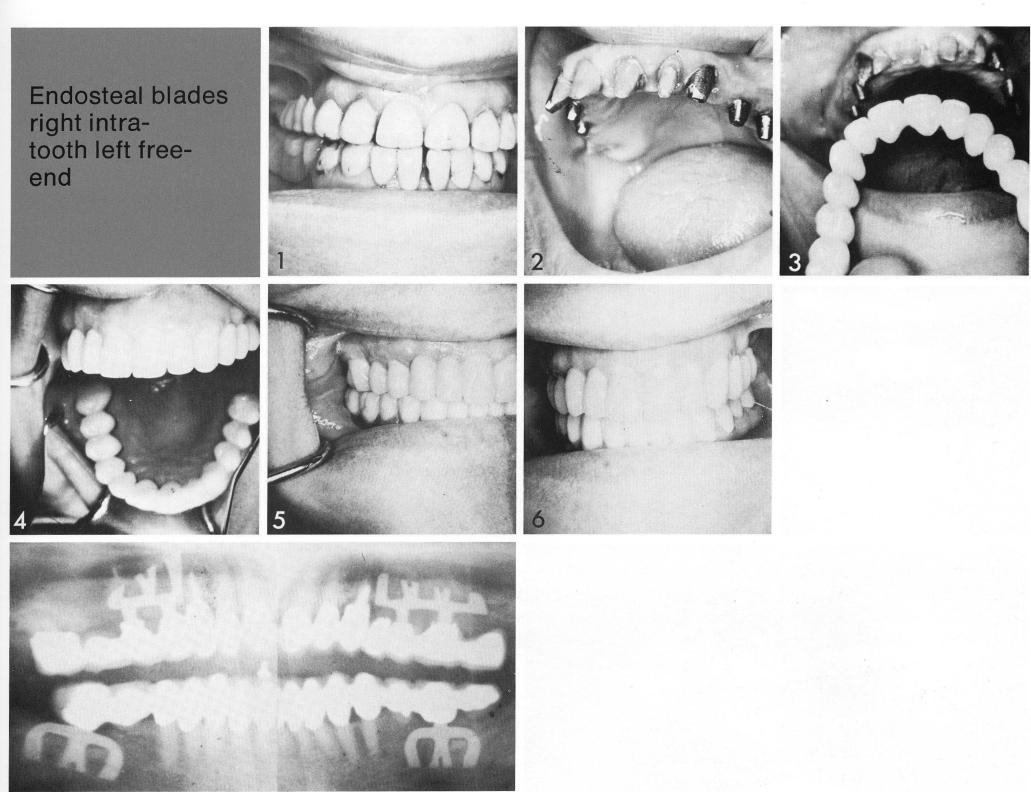

Endosteal blades

right intratooth left free-end

In this patient two types of sinus-circumventing bladevents were used bilaterally. The patient's own natural anterior teeth were unattractive (I), so a full-arch restoration was planned. The natural and artificial abutments (2) provided ample support for the attractive full-arch replacement (3,4), the occlusion of which was carefully balanced (5,6) to avoid traumatic displacement of both natural and artificial abutments.

1 Maxillary sinus circumventing bladevent implants used bilaterally